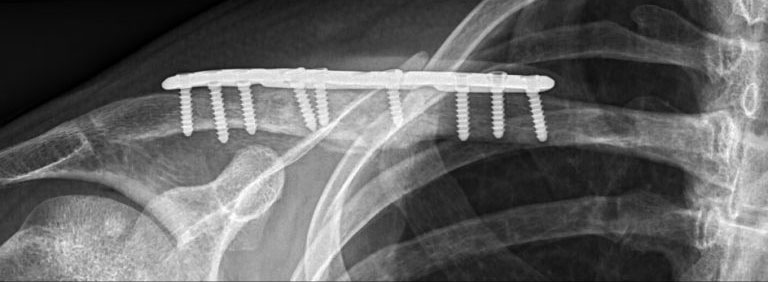

Matt fractured his clavicle in 2019, breaking the bone into 4 separate pieces. He was initially treated without surgery, causing the bone to heal in a displaced and abnormal position as seen on the X-ray image above. Healing in this way is described as malunion.

During the surgery I made two separate cuts in the bone, allowing it to be repositioned and brought out to its correct length. The position of the cuts (or Osteotomy sites) were determined from his original fracture and from the 3D model. The newly aligned clavicle was held in place with a plate and screws, and excess bone was used as graft to stabilise the position and encourage healing of the bone. X-rays taken during and after the operation showed that the clavicle was back in its anatomical position.

X-rays taken during and after the operation showed that the clavicle was back in its anatomical position.